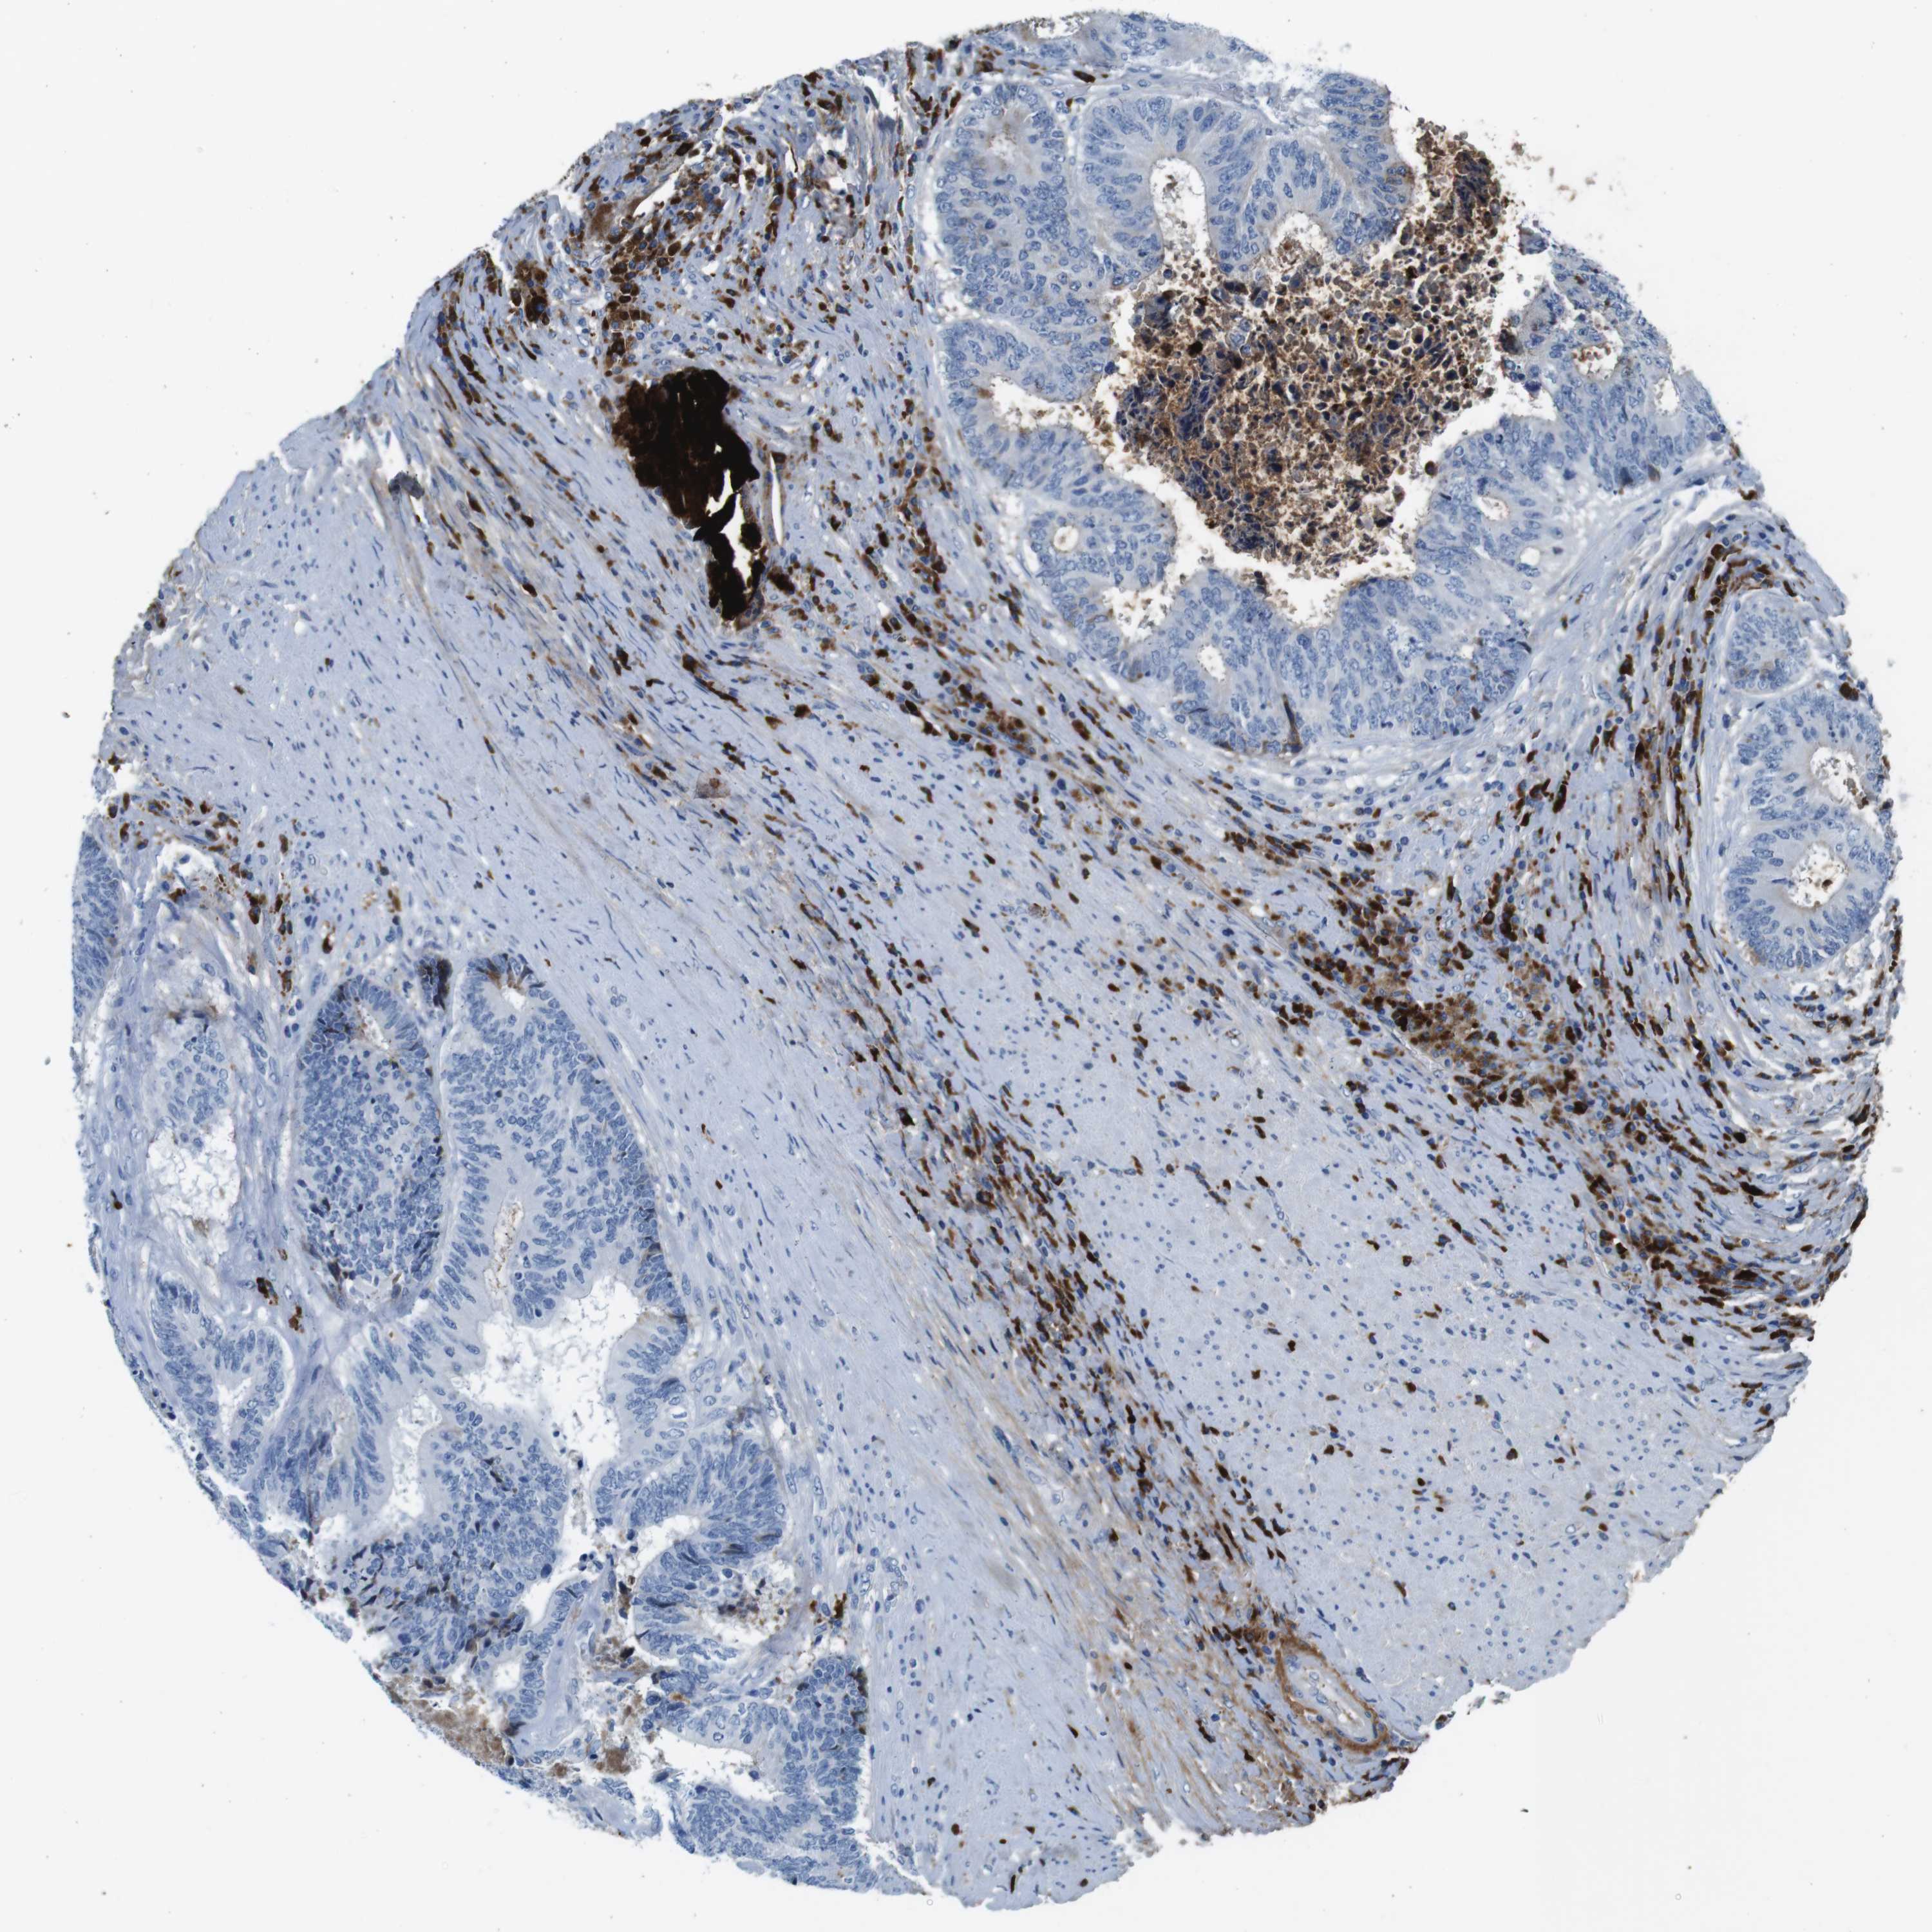

CANCER COLORECTAL CANCER Show tissue menu

Colorectal cancer

Human cancer

Colon adenocarcinoma